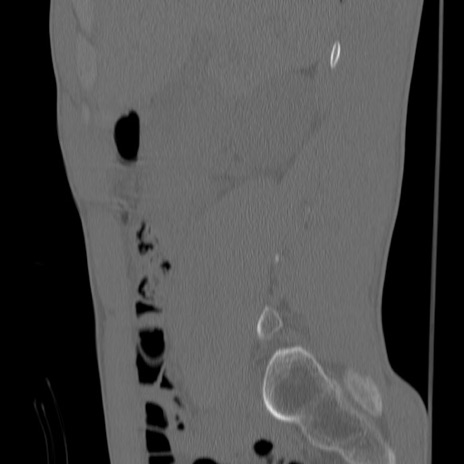

症例3 腰椎CT(矢状断像)

【症例】30歳代男性

【主訴】腰痛

【現病歴】本日旅行先で観光中に、友人と衝突し転倒し受傷。

【身体所見】麻痺なし、右下腿内側前面外側、左下腿内側に知覚鈍麻・しびれ

異常所見と診断は?

腰椎CT